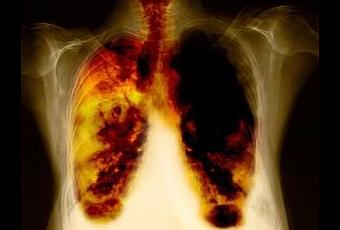

Tratamientos alternativos para curar el Cáncer de Pulmón